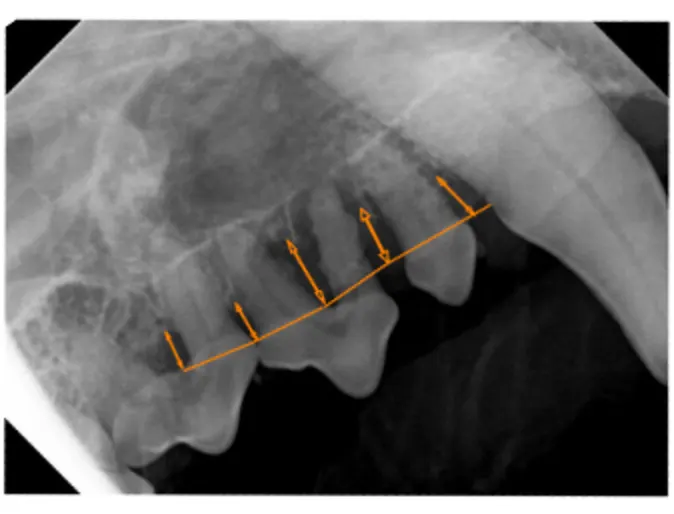

Major bone loss on multiple teeth indicated by orange arrows. These teeth are very loose on exam.

Teeth are almost completely obscured by tartar and pus is evident in many places.